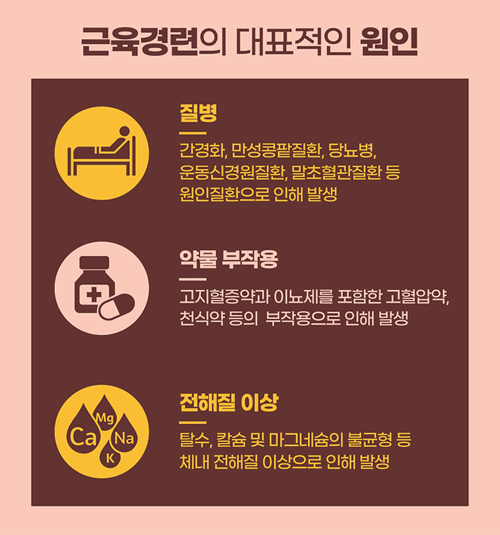

1. 갑작스러운 근육 경련의 원인은 무엇인가요? 이와 관련해 어떤 이는 마그네슘 결핍 때문이라고 말하는 반면, 어떤 이는 근육질환을 생각하며 불안에 사로잡혀 근육이 점점 약해지고 있다. 근육이 마음대로 움직이는 이유는 무엇입니까?

오하이오 주립 대학 웩스너 의료 센터에 따르면 근육 떨림은 근육을 구성하는 섬유의 수축으로 인해 발생하며 얼굴, 팔뚝 및 다리에서 가장 흔합니다. 근육을 건강하게 유지하기 위해서는 일정 수준의 신경 자극이 필요하며, 신경 전달 과정의 균형이 무너지면 질병 발생 시 뿐만 아니라 일상생활에서도 근육 경련이 발생할 수 있습니다. 근육 경련의 원인에 대해 자세히 알아보십시오. 1) 스트레스: 불안과 스트레스는 근육 경련을 일으키는 신경 전달 물질을 방출하고, 불안으로 인한 과호흡은 체내 이온 농도를 변화시켜 근육 떨림을 유발합니다.

2) 수면 부족: 수면은 신체 재충전을 돕습니다. 수면 부족은 호르몬 불균형을 유발하고 신경 전달 물질의 작동 방식에 영향을 미쳐 근육 경련을 유발할 수 있습니다.

3) 카페인: 과도한 카페인 섭취는 불면증, 신경과민 및 근육 경련을 유발할 수 있습니다. 간단히 생각해보면 과도한 카페인은 배터리를 정해진 용량 이상으로 충전하는 것과 같아서 신경과 근육의 이상을 일으키는 것과 같습니다.

4) 탈수: 물을 충분히 마시지 않거나 땀을 많이 흘리면 체수분 손실로 근육경련이 생길 수 있다. 또한 근육 경련은 영양 결핍, 갑상선 호르몬, 코르티솔과 같은 호르몬 불균형, 특정 약물 복용 또는 신경학적 문제로 인해 발생할 수도 있습니다.

근육 경련을 예방하려면 신선한 과일, 채소 및 견과류와 함께 건강한 식단을 섭취하고 매일 밤 최소 7-8시간의 수면을 취하십시오. 또한 카페인이 함유된 에너지 드링크, 커피, 홍차 등을 피하고 물을 많이 마시되 운동이나 더운 날씨에 땀을 많이 흘리기 때문에 섭취량 조절이 필요하다. 하루에 30~45분 정도 적당한 운동을 하면 근육 경련을 예방할 수 있으므로 자신의 몸에 맞는 것을 찾는 것이 가장 좋습니다. 근육떨림이 물, 식이요법, 운동 등으로 호전되지 않거나, 장기간 지속되거나, 신체 여러 부위에 발생하거나, 새로운 약을 복용한 후 떨리거나, 발열, 메스꺼움, 구토, 두통, (출처: 하이닥 ‘갑작스런 근육경련이 왜? 권예진 기자) 2. 팔근육경련 – 대부분의 사람들은 다리나 팔, 손가락이 이유 없이 떨리면 당황스러울 수 있다. 건강 걱정은 안해도 될 것 같아요. 발이나 팔의 경련은 부차적인 원인일 수도 있지만 의학적 상태의 징후일 수 있습니다. 팔 통증의 원인, 팔 근육이 아픈 시기와 이유에 대해 자세히 살펴보겠습니다. *팔 근육의 경련성 통증의 원인 1) 근긴장이상 – 목, 얼굴 등의 근육과 사지의 근육이 자신의 의지와 상관없이 수축하고 뒤틀리는 경우 근긴장 이상을 의심해볼 수 있습니다. 움직일 때는 나타나고 움직이지 않을 때는 나타나지 않으며, 심할 경우 뒤틀린 증상이 나타나게 됩니다. 아직 확실한 근거는 밝혀지지 않았지만 대뇌 피질의 기능 변화나 신체 특정 부위의 감각 변화가 그 근거가 될 것이라는 가설이 제기되고 있다. 증상이 심하고 관절이 변형될 수 있다면 전문의의 진료를 받는 것이 좋습니다. 2) 파킨슨병 – 안정시에 발생하는 떨림을 안정떨림이라고 합니다. 글을 쓰거나 젓가락이나 숟가락을 사용할 때 증상은 없지만 안정시 떨림은 안정시 팔이 떨리는 현상입니다. 이러한 증상이 나타난다면 파킨슨병을 의심해볼 수 있습니다. 파킨슨병은 시간이 지남에 따라 악화되며 떨림 외에 근육 경직, 균형 상실, 느린 움직임을 포함할 수 있습니다. 파킨슨병은 조기 발견이 중요하므로 진단을 받는 것이 중요합니다. 3) 스트레스와 수면부족 – 심한 불안과 스트레스는 몸에 변화를 가져오는 경우가 많다. 장기적인 정신 문제로 고통받는 경우 신경 전달 물질이 방출되고 근육이 경련을 일으킬 수 있습니다. 불안으로 인한 과호흡도 접지되어 팔 근육에 떨림을 유발할 수 있습니다. 수면 부족은 또한 신체에 악영향을 미쳐 종종 호르몬 불소화로 이어질 수 있습니다. 그 결과 신경 전달 물질이 오작동하고 근육 경련이 자주 발생합니다. 4) 탈수, 카페인 섭취 – 물을 충분히 마시지 않거나 땀을 많이 흘리면 팔 근육이 순식간에 경련을 일으킨다. 커피나 콜라를 많이 마시면 신경과민, 불면증, 팔 근육 떨림 등의 증상이 나타날 수 있다. 이러한 떨림은 특정 약물을 복용할 때나 신체에 영양분이 부족할 때도 발생할 수 있습니다. 또한 팔 근육 경련 증상의 기본은 마그네슘과 나트륨 부족입니다. 근육 경련을 예방하려면 적절한 수분 섭취, 휴식 및 균형 잡힌 영양 섭취가 필수적입니다. 증상이 지속되고 메스꺼움, 두통, 구토, 발열 등의 증상이 나타나면 제때 병원에 내원하여 치료를 받아야 하며, 경우에 따라 수술을 고려할 수도 있습니다. 수술방법으로는 시상면파괴나 뇌심부자극술이 개발되어 시행되고 있다. (출처: 삼성서울병원 뇌신경센터)